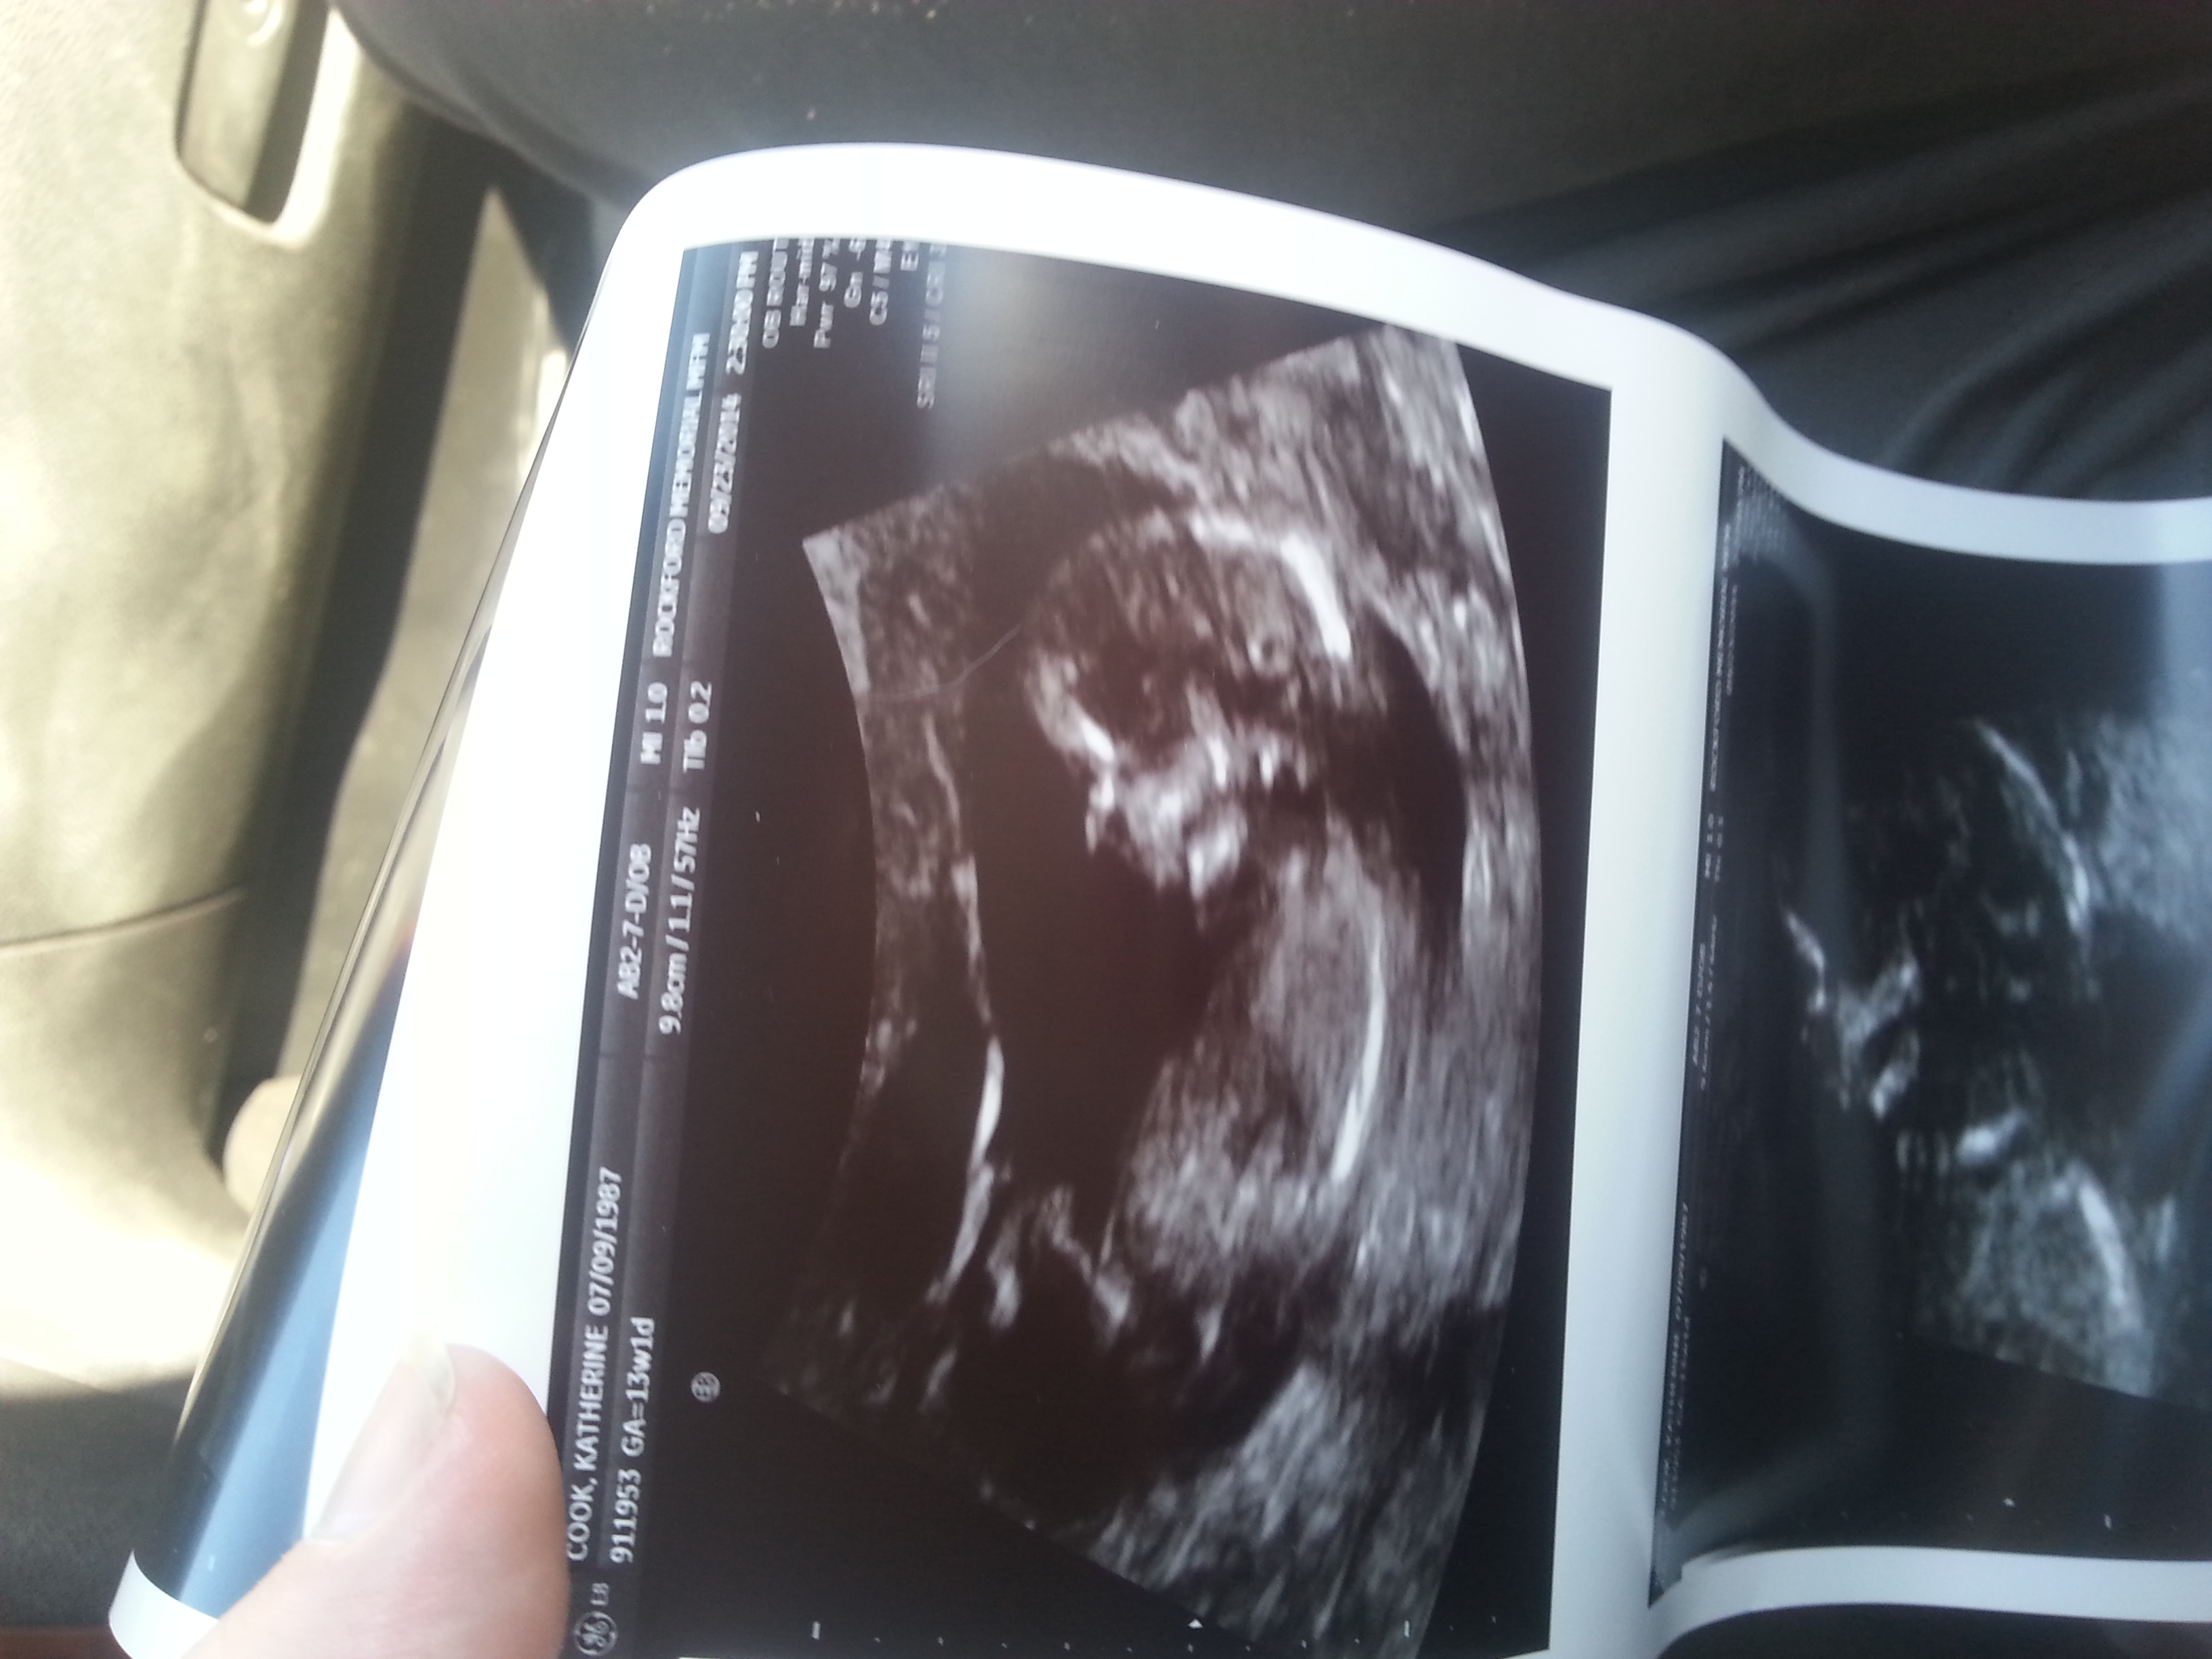

Was told 4th boy today. .13 weeks 1 day